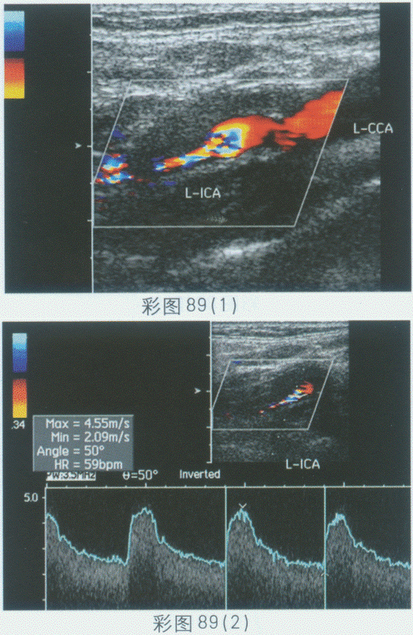

临床资料:男,68岁,确诊糖尿病20年,脑梗塞5年。超声综合描述:双颈总、颈内动脉内膜粗糙,回声强弱不均,中内膜不均匀增厚;左颈内动脉起始段管壁可见中等回声区,后方无声影,该段残余管腔内径0.33cm,CDFI:左颈内动脉起始段中等回声区内血流充盈缺损,残余管腔内可见细小血流通过,其远端呈杂色血流信号,PW:该段V4.55m/s。见彩图89。

超声提示()。

A.双侧颈动脉粥样硬化并左颈内动脉起始段软斑形成并节段性管腔狭窄

B.双侧颈动脉粥样硬化

C.双侧颈动脉粥样硬化并硬斑形成

D.正常颈动脉声像图

247、单项选择题 正常腮腺的声像图表现是()。